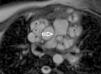

A 21-year-old woman was admitted to our clinic with dyspnea. Her medical history was unremarkable. Right bundle branch block was identified on 12-lead ECG and mediastinal enlargement on the chest X-ray. Transthoracic and transesophageal echocardiographic examination showed a lobulated cystic image in the left atrium and secundum-type atrial septal defect (Figures 1 and 2). Additionally, in short-axis view a mass was visualized invading the pulmonary artery, and continuous wave Doppler of the pulmonary artery revealed a maximum gradient of 40 mmHg. A detailed examination with cardiac magnetic resonance imaging demonstrated a multicystic mass in the mediastinum compressing the main pulmonary artery, predominantly the left branch (Figure 3). The patient was diagnosed with secundum atrial septal defect and mediastinal hydatid cyst on the basis of serologic tests and detailed history. Surgical therapy was offered and she asked for time to think. Medication with albendazole was started, but she was then lost to follow-up.